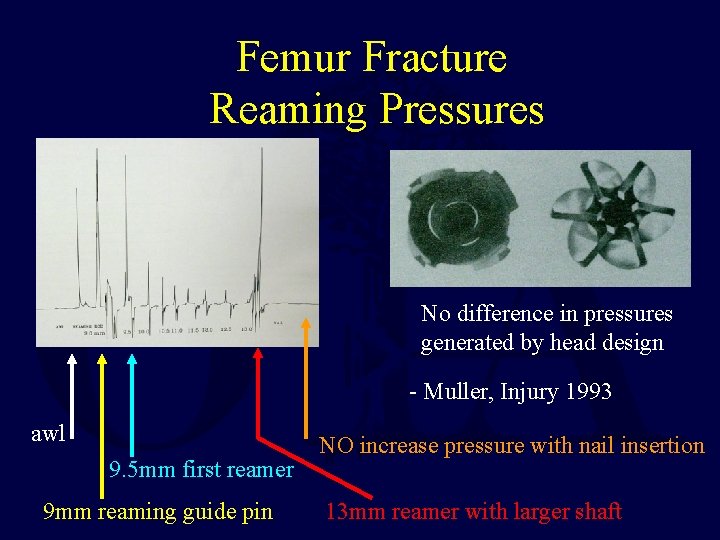

Femur Fracture Reaming Pressures No difference in pressures generated by head design - Muller, Injury 1993 awl 9. 5 mm first reamer 9 mm reaming guide pin NO increase pressure with nail insertion 13 mm reamer with larger shaft